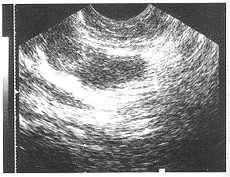

使用仪器为德国Performa及东芝350彩超仪,探头频率 6.5 MHz,配穿刺导向器,穿刺针为日本产21G 200 mm多侧孔治疗针。术前检查尿、精液、大便常规及出凝血时间。穿刺前 3 d口服抗生素,穿刺前 1 h用生理盐水 250 ml加庆大霉素 32 万单位清洁灌肠。患者取左侧卧位,肛门部及直肠常规消毒,探头涂少量耦合剂,套消毒套,安装穿刺导向器后缓慢插入直肠,穿刺针经穿刺导向器刺入精囊,抽取精囊液涂片送检验及细菌培养,进一步确定病原菌,指导诊断及治疗。然后用灭滴灵 250 ml反复冲洗精囊,彩超可见药液扩散情况(图1),注入丁胺卡那霉素 0.4 g保留。对伴有精囊囊肿的患者,穿刺囊肿抽净囊液,注入无水酒精硬化治疗。术后口服抗生素 3 d。

图1 注药时用彩超观察可见药液扩散